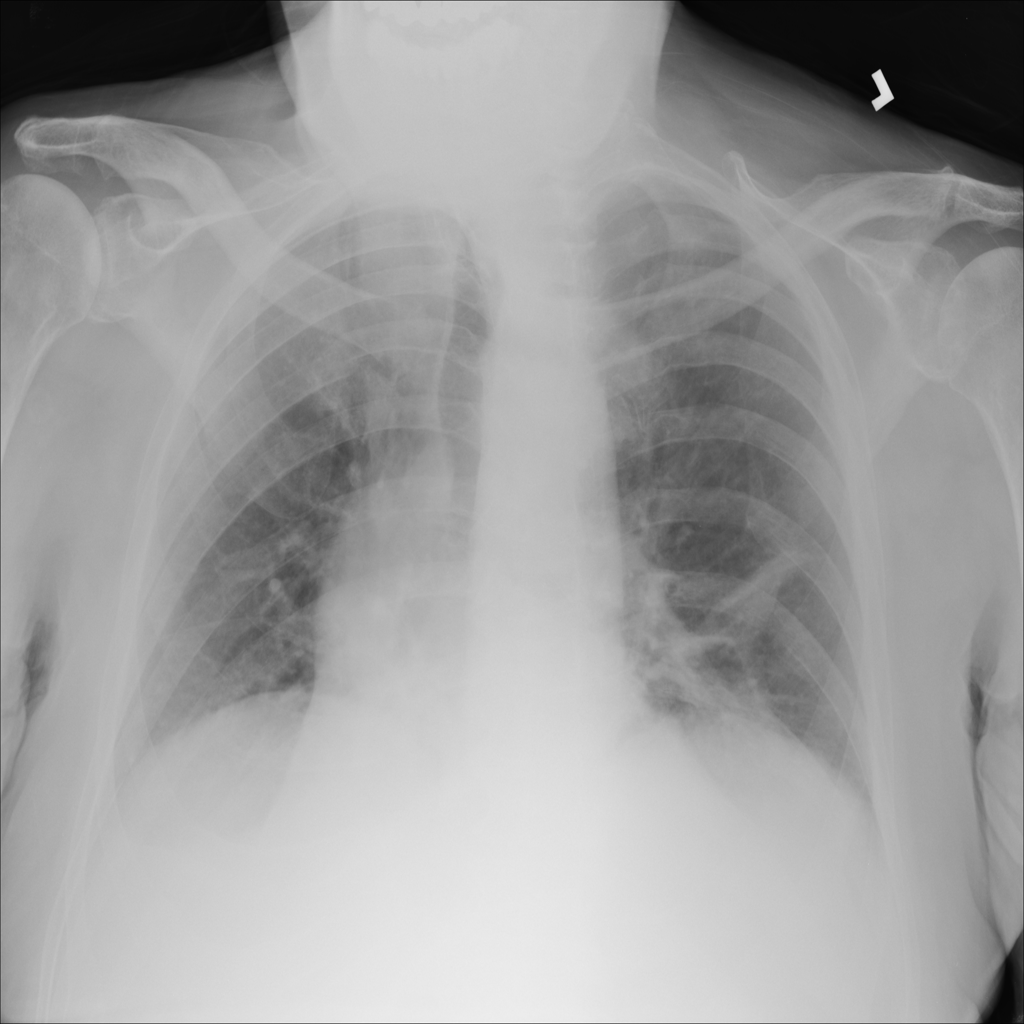

PAT-B3C3 · IMG-001Pneumonia

PAT-B3C3 · IMG-001

PA